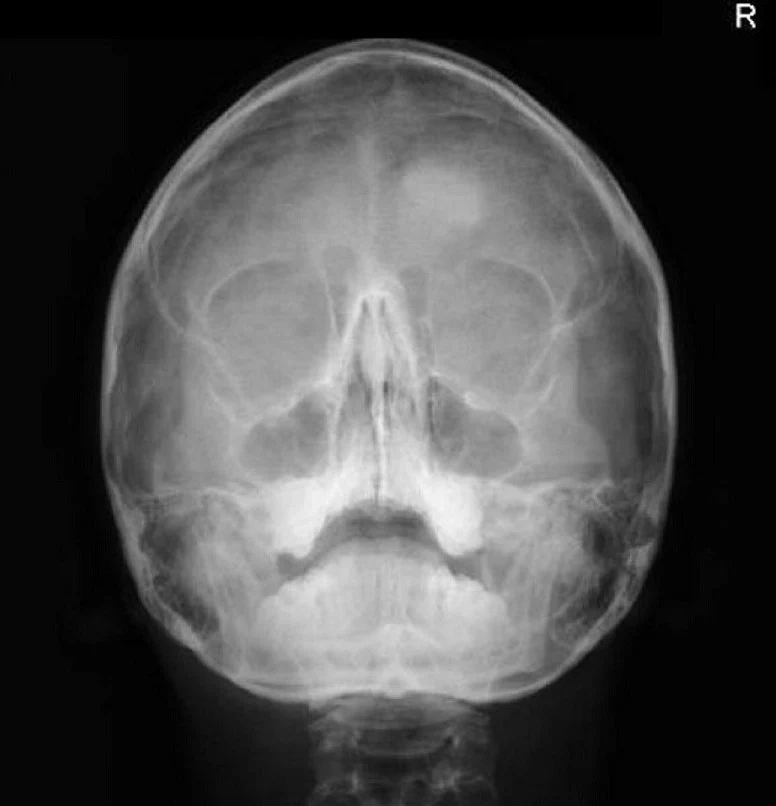

RX PERFILOGRAMA DOS PROYECCIONES (NARIZ) + WATERS

RPERFIL2